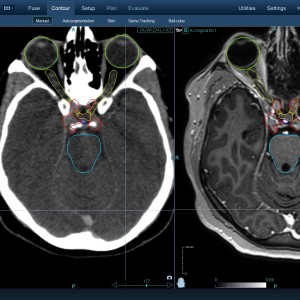

Στις παρακάτω φωτογραφίες θα δείτε παραδείγματα πλάνων θεραπείας καρκινικών όγκων με CyberKnife. Παρατηρήστε πόσο κοντά στους υγιείς ιστούς βρίσκονται οι καρκινικοί όγκοι που χρειάζεται να ακτινοβοληθούν. Μόνο με το CyberKnife και το προσωπικό πλάνο θεραπείας, μπορούν να ακτινοβοληθούν οι όγκοι χωρίς να πληγούν οι παρακείμενοι υγιείς ιστοί.

Με κόκκινο χρώμα περιγράφεται η περιοχή του όγκου.

Με μπλε, κίτρινο και πράσινο χρώμα περιγράφονται οι υγιείς ιστοί που δεν πρέπει να ακτινοβοληθούν.

Παρατηρήστε πόσο κοντά βρίσκεται ο όγκος με τους υγιείς ιστούς.